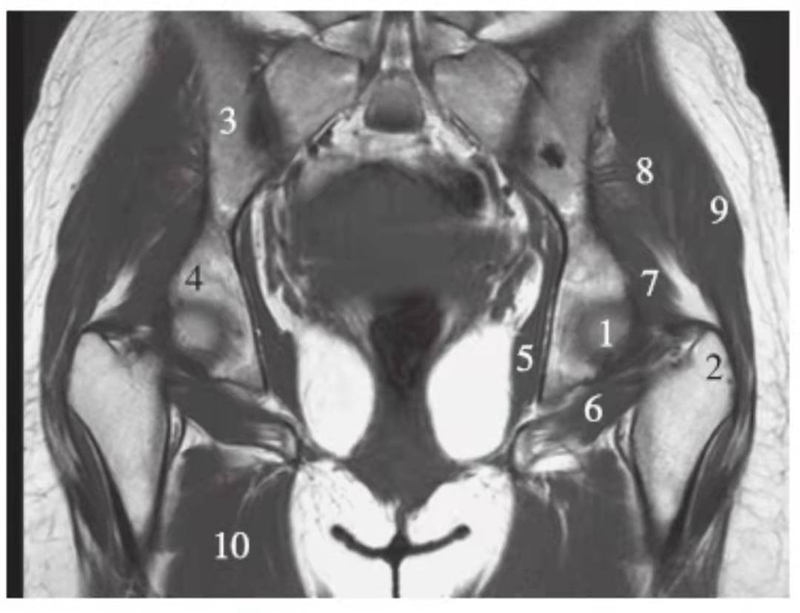

冠状位

正常髋关节经股骨头后缘层面T1WI像

1.股骨头;2.大转子;3.髂骨;4.坐骨;5.闭孔内肌;6.闭孔外肌;7.臀小肌;8.臀中肌;9.臀大肌;10.内收肌群